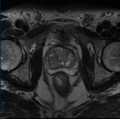

• Segmentation of prostate and its sectors

• Specifically, segmentation of the following prostate sectors: peripheral zones, transition zones, central zone, anterior fibromuscular stroma and urethral sphincter